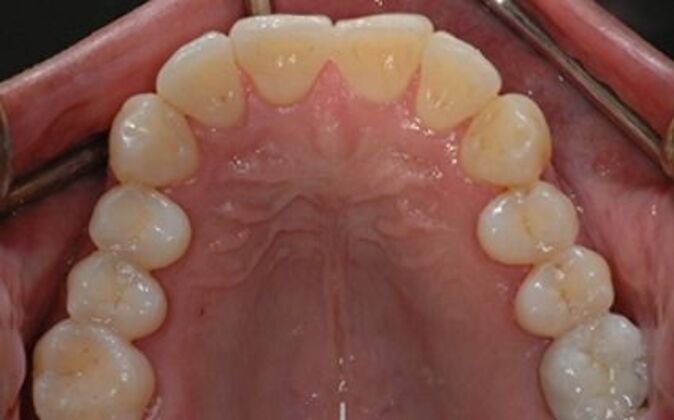

Like our recent patient, Joe Parvenah was a member of our extended family who had been dissatisfied with her previous dental work. Her original dentist was well-known, and had been highly recommended. But his years of treatment had failed to address her numerous problems properly and, as a result, they had (as they always do) gotten worse over time. By the time Parvenah decided to come in for a consult, we found some serious issues that needed attention: she had broken implants in her bone that was never removed, and had been left with ill-fitting dental bridges that had completely infected her teeth, leaving her with abscesses that would not heal. Unfortunately, to repair the damage and neglect, we had to first remove more teeth and rejuvenate her entire mouth from scratch. If we hadn’t realized the extent of her problems, she would have soon needed full dentures. With the help of our specialist, Dr. David Weinstein, we were able to create a treatment plan that would cure the infections first, and then add a series of dental implants that would distribute her bite forces evenly and with less trauma to her remaining teeth. Parvenah’s reconstruction was extremely difficult because her jaw bone was very thin to begin with, and needed a highly-trained implant dentist who could place the required implants successfully, even with compromised bone. Although it took about twelve months to complete Parvenah’s reconstruction, the outcome left her pain- and infection-free for the first time in years, and enjoying beautiful, functional new teeth that would withstand years of service. Once again, as with Joe, we were gratified to be able to improve the life and health of a family member.